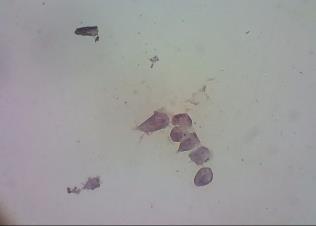

The observation of expression of cell cycle regulator protein Cyclin D1 and angiogenic factor protein COX-2 was conducted in T47D cells by using PAE and doxorubicin, both a single application or in combination of them. In this study, the effects of PAE, doxorubicin and their combination on cyclin D1 and COX-2 were evaluated by using immunocytochemistry. The expression of cyclin D1and COX-2 proteins is positive characterized by brown stained nuclei in the cells (fig. 3 and fig. 4). High intensity of brown colour was shown on untreated cells (negative control) for cyclin D1 and COX-2 proteins. A single treatment of PAE decreased the cyclin D1 and COX-2 proteins expression. Single treatment of doxorubicin did not decrease cyclin D1 and COX-2 expression. However, the combination of PAE and doxorubicin was decreased these proteins expressions.

Fig. 3: Expression of cyclin D1 on T47D cells using immunocytochemistry. (a) control cells; (b) PAE 8 µg/ml; (c) doxorubicin 1 µg/ml; (d) combination of PAE 8 µg/ml and doxorubicin 1 µg/ml

![]() |

(a) |

(b) |

(c) |

(d) |

Fig. 4. Expression of COX-2 on T47D cells using immunocytochemistry. (a) control cells; (b) PAE 8 µg/ml; (c) doxorubicin 1 µg/ml; (d) combination of PAE 8 µg/ml and doxorubicin 1 µg/ml. ( positive expression; negative expression)

The expression of cyclin D1 of either single treatment or their combination strengthen the information about the effect of them on cell cycle accumulation especially in inhibition of cell cycle on G0-G1 phase. Cyclin D1 play an important role in G0-G1 phase. The complex of cyclin D1 with CDK-4 or CDK-6 controlled G1 to S phase transition. Despite combination of PAE-doxorubicin could inhibit the cell cycle by decreasing level of cyclin D1, it resulted inhibition of pRb phosphorylation. So, E2F cannot a part from pRb, and cells can not transcribes genes which is needed in cell cycle process or cell proliferation[7, 8].

Both single treatment and combination of PAE-doxorubicin did not express of COX-2 protein. It may be caused by ursolic acid effect which is known decrease the expression of matrix metallo-proteinase-9 (MMP-9). Matrix metalloproteinase activities are involved in the remodelling of the extracellular matrix, part of the tumor micro-environment, and are thus linked to tumor invasion and increased risk of metastasis [11].